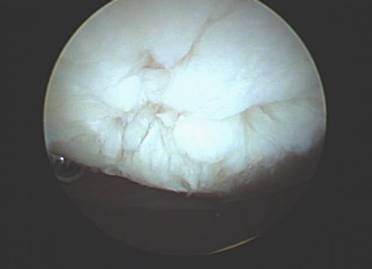

Within the knee joint synovial fluid is highly viscous which provides a friction-free environment. Hyaluronic acid (HA) which is present in our synovial fluid is also found in most body tissues. In a healthy adult, synovial fluid HA has a molecular weight of 4-5 million. As a result of this large size HA molecules entangle, forming coiled configurations which in turn provide elasticity and viscosity to synovial fluid. HA also binds to proteoglycans to stabilize the structure of the articulate cartilage. In patients with OA, the molecular weight of the HA decreases causing the synovial fluid to become less viscous thus leading to increased friction and abnormal joint movement.

When exercises fail to improve the knee then surgery may be indicated if the symptoms are significant enough to alter activities. The most common arthroscopic surgical procedures to treat chondromalacia include chondroplasty and microfracture / abrasion procedure. A chondroplasty involves smoothing out roughened surface cartilage which can decrease friction forces on the surface cartilage and decrease symptoms of chondromalacia. An abrasion or microfracture is most useful when there is a small contained area of exposed bone or complete loss of surface cartilage. During this procedure the bone is tapped with a pick-type tool which causes bleeding in the area of exposed bone. This blood from deep inside the bone carries stem cells which can cause the bone to grow a scar type cartilage. This scar cartilage has been shown to be very effective in reducing knee pain in several orthopedic studies.